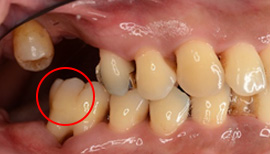

エムドゲインと骨造成による歯周再建

エムドゲインによる歯周再生治療 骨造成併用

Before

After

| 主訴 | 歯肉が腫れてグラグラする |

|---|---|

| 治療期間・回数 | 約2~3ヶ月・6回 |

| 費用 | 150,000円 |

| デメリット・注意点 | 術後に腫れる可能性がある。 |

失われた歯周組織をエムドゲインで再生へ導く